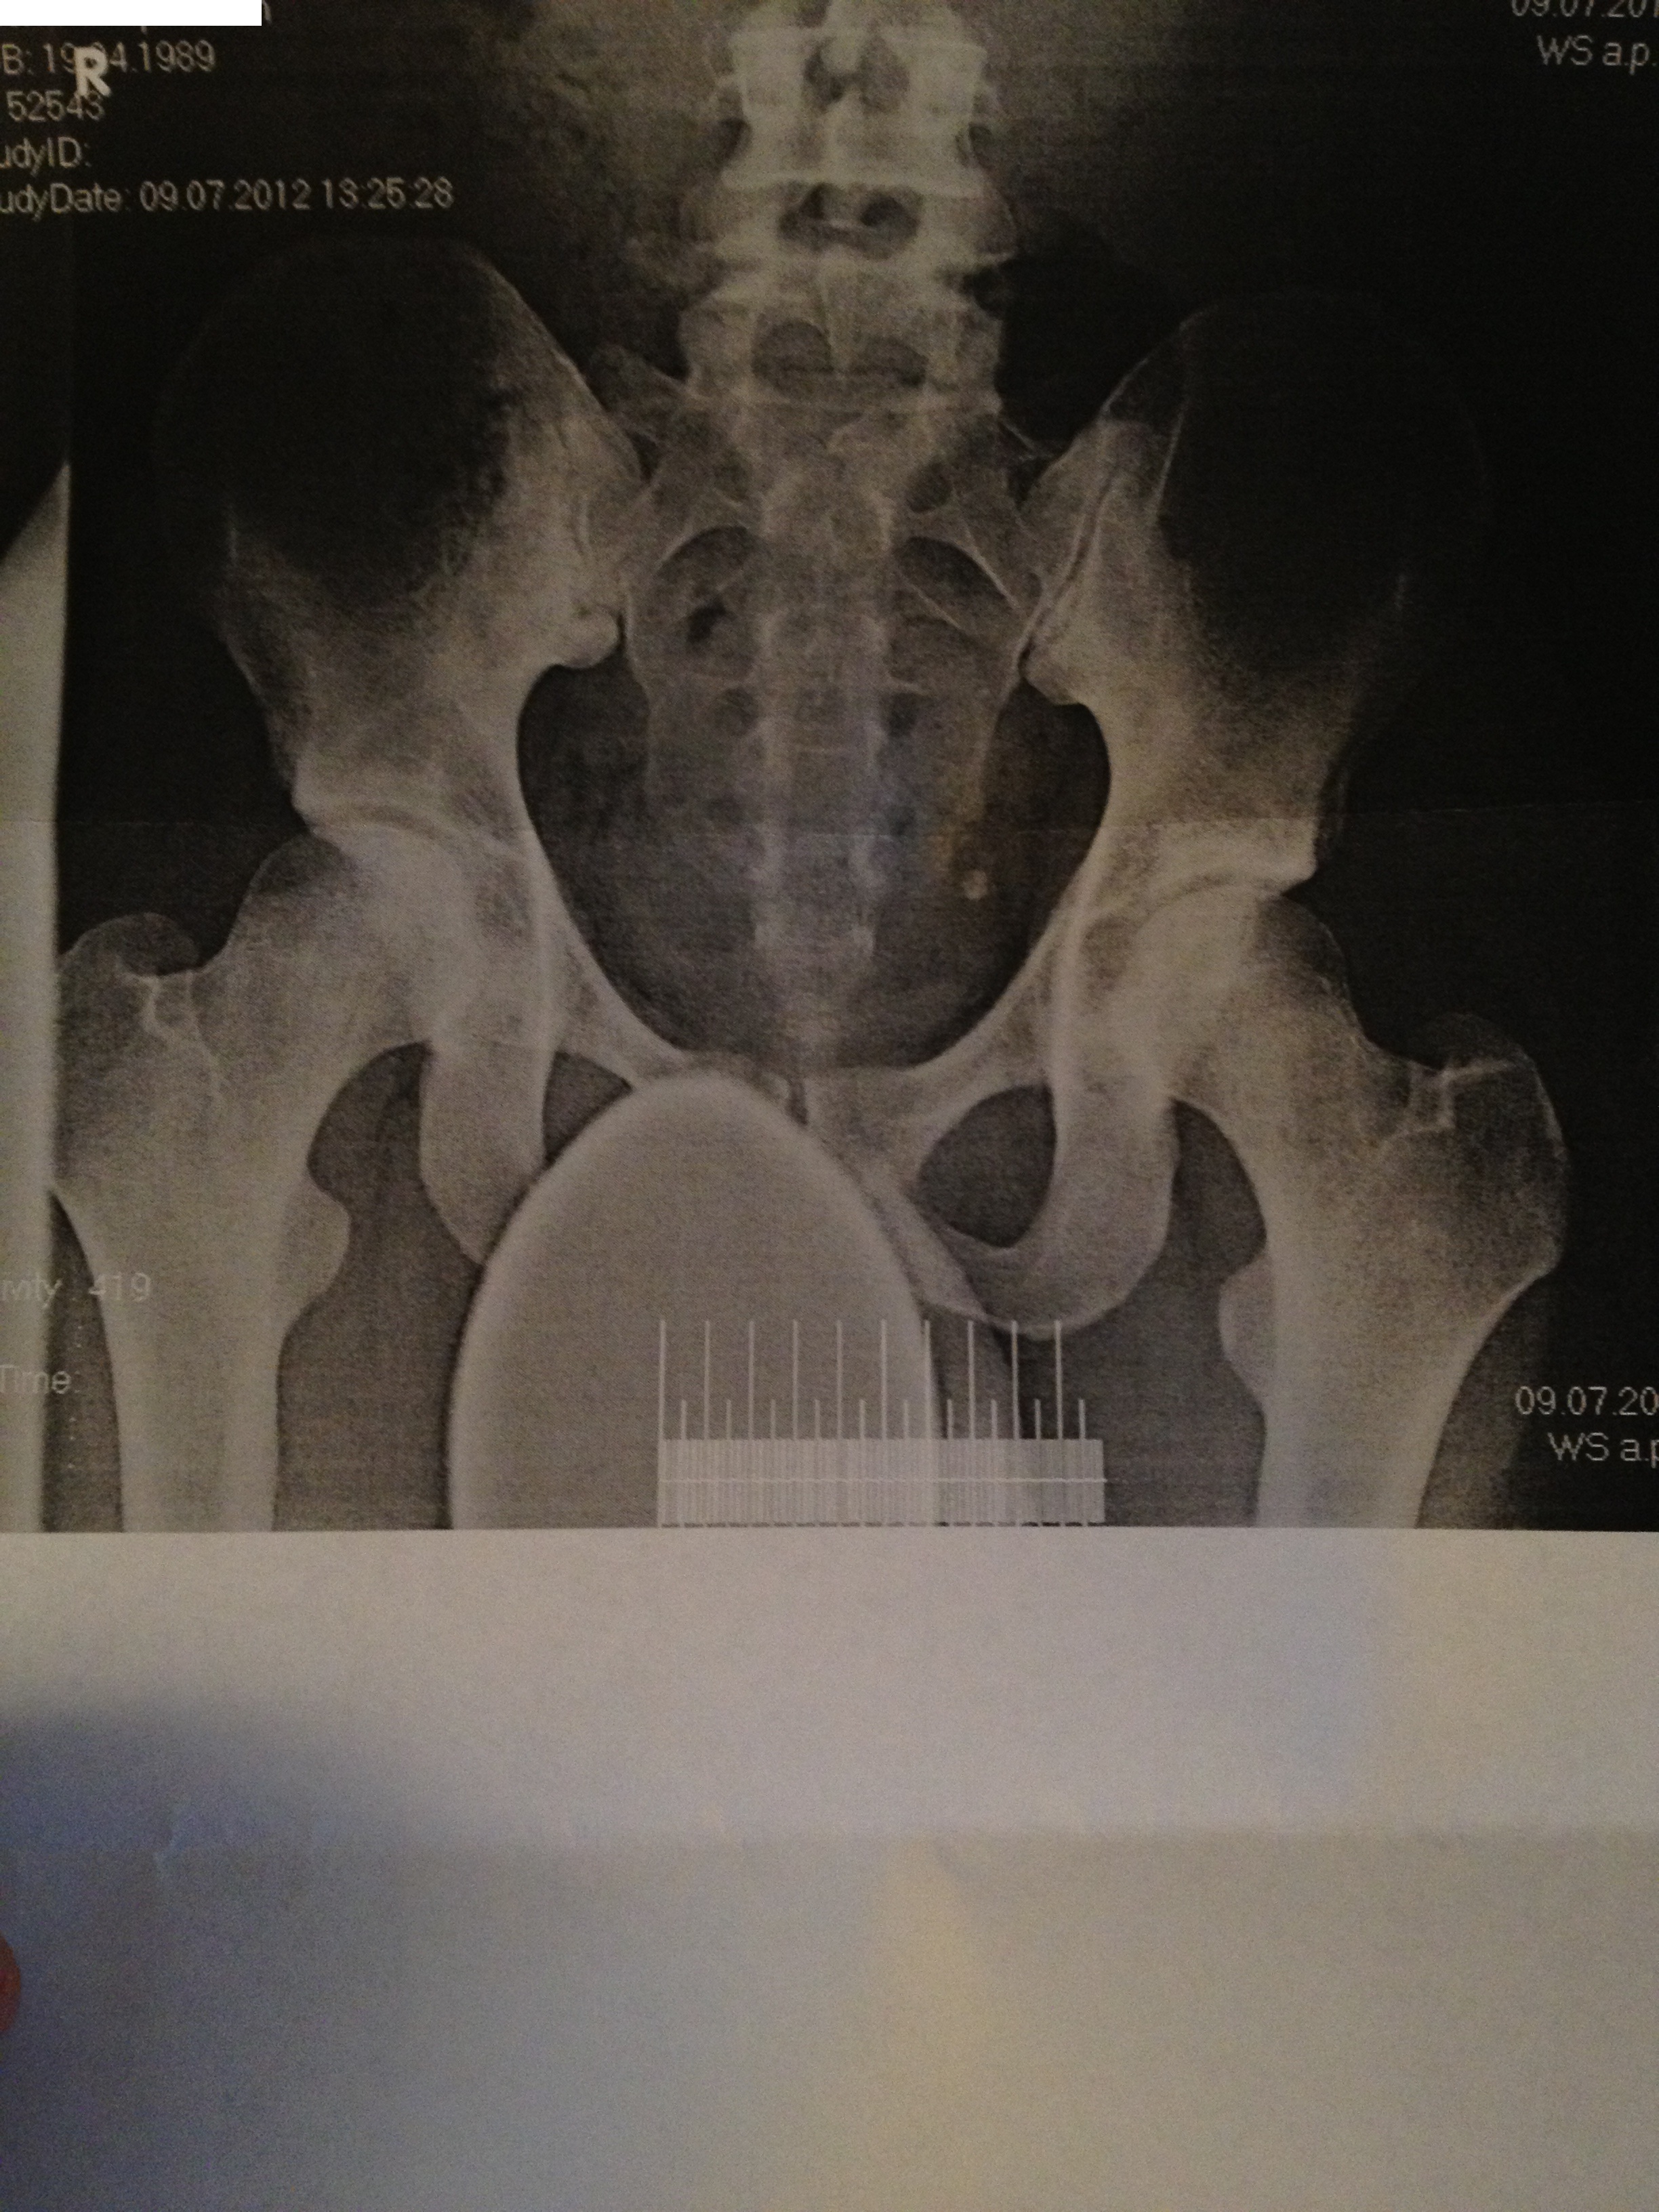

Röntgen becken http://s14.directupload.net/images/130207/ukros3s9.jpg

Also für ich sieht das ganz normal aus, nen leichten Beckenschiefstand kan nman erkennen, aber mehr sehe ich da nicht.

Anhand deiner Röbis kann man schon ein Hohlkreuz erkennen. Hast du denn auch Schmerzen und was hast du bislang gegen dein Hohlkreut getan? Hast du KG gemacht?

ich habe mir Deine Bilder angesehen, und finde auch wie Kaffeetrinker außer einen leichten Beckenschiefstand nichts

eine Hyperdorlose kann ich bei dir leider auch nicht sehen. Deinen Beckenschiefstand schon.